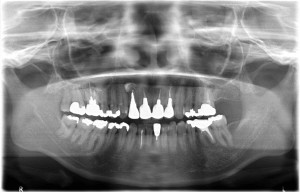

術前レントゲン写真

-